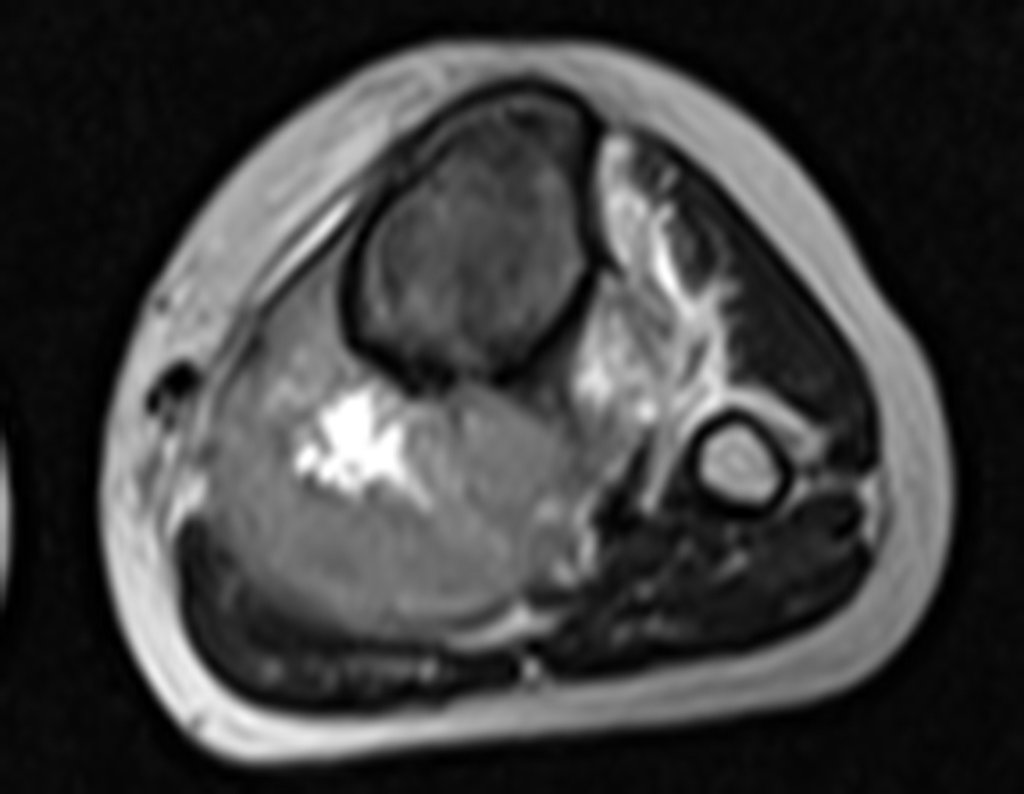

Ingresó en el hospital en mayo y se sometió a una biopsia por punción. El informe anatomopatológico indicó osteosarcoma central convencional localizado, con cultivos negativos. Se le realizó estadificación con TC de tórax, gammagrafía ósea de todo el cuerpo y resonancia magnética del miembro inferior derecho. Se le realizaron tres ciclos de quimioterapia neoadyuvante con Platino y Doxorrubicina, con buena respuesta.